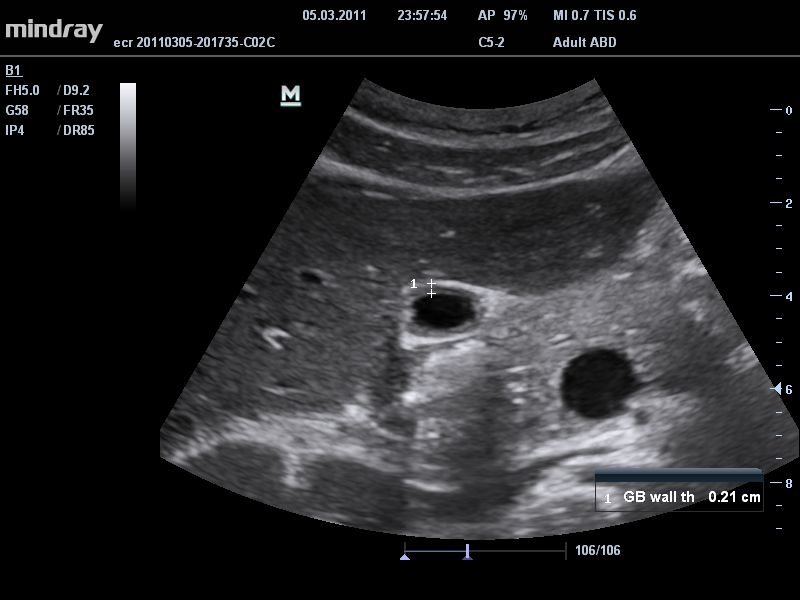

• THI со сдвигом фазы: увеличивает четкость визуализации желчного и мочевого пузыря и повышает отношение сигнал-шум.